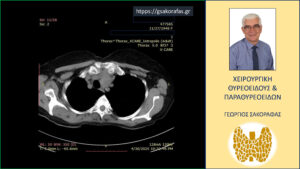

Αξονική τομογραφία

Η ασθενής υποβλήθηκε σε αξονική τομογραφία προκειμένου να αξιολογηθεί το βάθος κατάδυσης του καταδυόμενου όζου στον θώρακα. Παρατηρείται σημαντική διόγκωση του αριστερού λοβού που καταδύεται στο μεσοθωράκιο επεκτεινόμενος οπισθίως της τραχείας την οποία και απωθεί προς τα δεξιά.